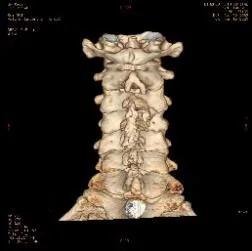

颈后路术后颈椎CT。

后入路术后见颈部椎管后方减压范围满意,骨性结构破坏小。

颈前路术后颈椎CT

前入路术后见颈椎间盘突出组织摘除完全。闫先生经住院治疗15天出院,治疗效果非常满意。